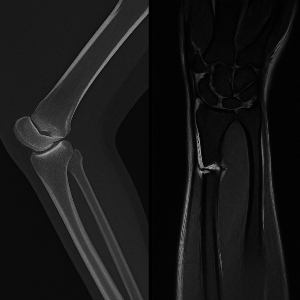

골절이 의심될 경우, 가장 먼저 고려되는 검사는 CT입니다. 이유는 간단합니다. 뼈는 방사선을 잘 흡수하기 때문에 X선을 이용하는 CT에서 매우 선명하게 나타납니다. 특히 미세 골절이나 복잡 골절, 관절 내 골절처럼 단순 X선으로는 확인하기 어려운 손상도 CT에서는 자세히 볼 수 있습니다.

예를 들어, 손목이나 발목의 작은 골절, 안면부 골절, 척추의 미세 골절 등은 X선으로는 간과될 수 있으나 CT로는 빠르고 정확하게 진단됩니다. 또한, 다발성 외상 환자의 경우 전신 CT를 통해 빠르게 전반적인 손상 정도를 파악할 수 있어 생명에 직결되는 판단에 큰 도움이 됩니다.